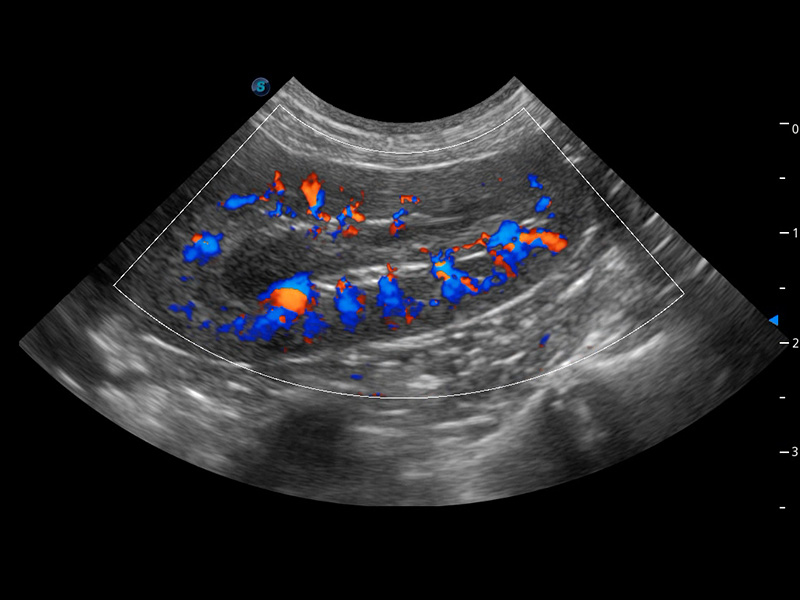

4T血流成像 微察秋毫

融合不同血流成像技術(shù)的優(yōu)勢(shì),即可以提升血流成束性,同時(shí)可提高血流的視覺(jué)敏感性。

PDI 能量多普勒血流

提供高靈敏度和空間分辦率的血流圖像,獲得更加真實(shí)和豐富的診斷信息。

SR Flow 高分辨率血流成像

能夠清晰顯示細(xì)小、低速血流圖像,獲取傳統(tǒng)彩色多普勒技術(shù)難以得到的細(xì)節(jié)和信息。

Micro F 顯微血流成像

通過(guò)創(chuàng)新的Matrix E自適應(yīng)濾波器和超長(zhǎng)時(shí)間域算法,極大提升超低速微細(xì)血流的檢出能力,同時(shí)更精準(zhǔn)地濾除軟組織和噪聲信號(hào),為獸用醫(yī)生提供以往無(wú)法通過(guò)常規(guī)血流獲得的疾病診斷信息。

Bright Flow 立體血流成像

在傳統(tǒng)二維血流成像的基礎(chǔ)上,呈現(xiàn)血流的立體感,具有動(dòng)感的生命力之美。精確區(qū)分不同血管的空間關(guān)系,提高了血流的視覺(jué)敏感性。

(犬)四腔心血流

(犬)腎臟血流